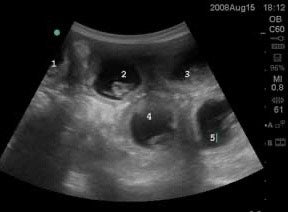

This picture shows 5 embryos inside each placental sac (the black area is the fluid around the stem embryo) and the placenta supplies nutrition and oxygen for the developing puppies.

Ultrasound pregnancy confirmation is possible as early as day 20-22, but can be missed this early. Ultrasound at day 30 post- mating is a great diagnostic tool to confirm pregnancy. Ultrasound has the drawback of not being accurate to count puppies, but can determine heartbeats in the puppies.